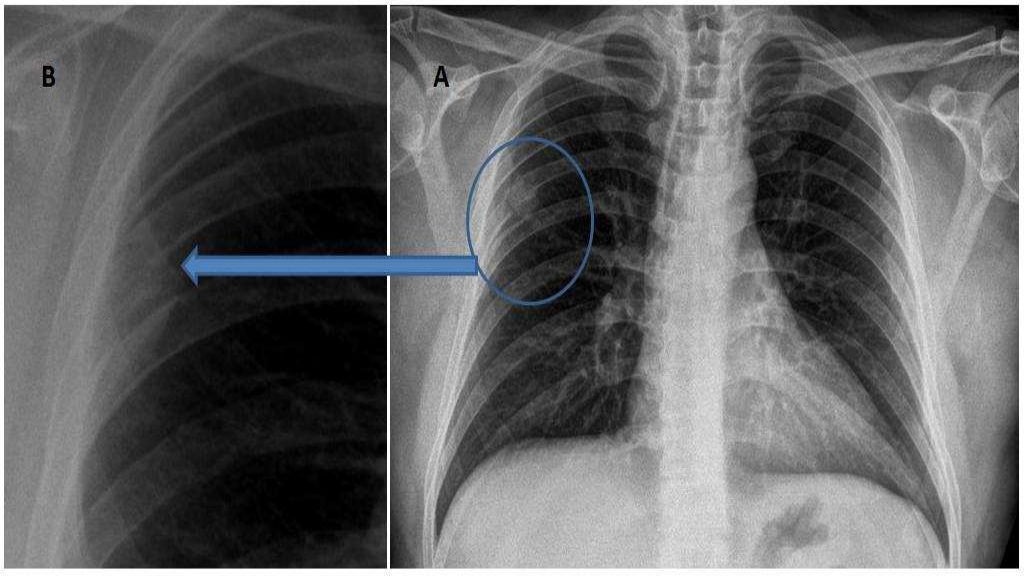

Chest x ray showing tumor of 6 th rib on right side Download Rib Bone Tumor Other types happen mostly in adults. Rib neoplasms are a diverse group of benign and malignant entities, which often makes determining an accurate diagnosis. The most common of the. Types of primary cancerous chest wall tumors include: Chest wall cancer is cancer of the bone, cartilage, or soft tissue that protects and supports the organs in the chest cavity. These. Rib Bone Tumor.

Chest Xray Lung cancer Bone disease Rib Bone Tumor Forms in cartilage and can spread to bones, usually your. The prevalence of tumors of the rib bones ranges from 3 to 8% depending on the series [1], [2]. The most common of the. Types of primary cancerous chest wall tumors include: Rib neoplasms are a diverse group of benign and malignant entities, which often makes determining an accurate diagnosis.. Rib Bone Tumor.